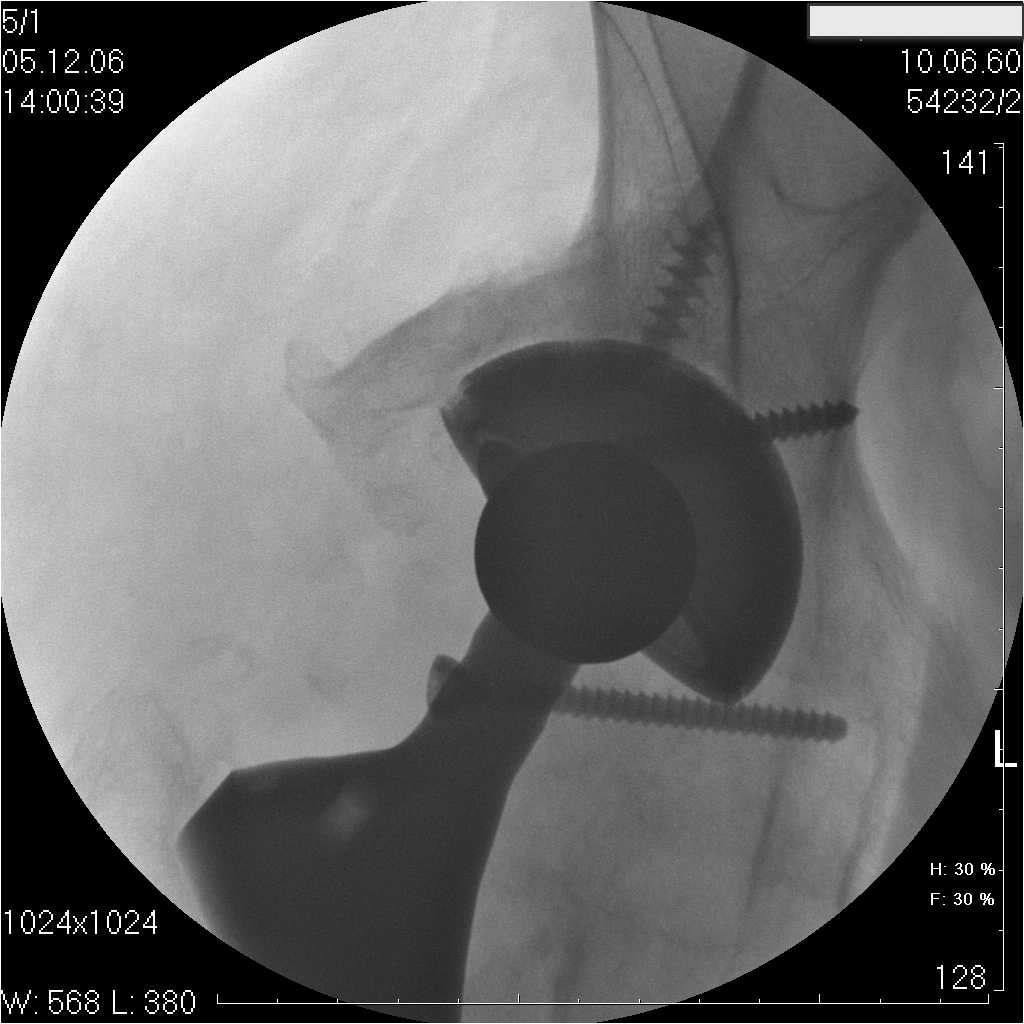

Уважаемые коллеги.В 3 Центральный Военный Клинический Госпиталь имени А. А. Вишневского, что в Красногорске, Московской области, в отделение эндопротезирования крупных суставов поступил пациент 1960 года рождения Жалобы при поступлении: на боли в области левого тазобедренного сустава (больной указывает на точку расположенная в середине условной линии между седалищным бугром и большим вертелом), усиливающиеся в начале ходьбы, при опоре на левую ногу с иррадиацией болей по наружной и наружно-задней поверхности левого бедра, левый коленный сустав; снижение объема движения в левом тазобедренном суставе, снижение опорной способности левой нижней конечности, хромоту на левую ногу, необходимость использования дополнительной опоры (костыли) при ходьбе, снижение объема двигательной активности из за болей в суставе.В анамнезе: Со слов больного, согласно медицинских документов, в 1989 году получил травму левой нижней конечности: закрытый перелом левой вертлужной впадины с центральным вывихом головки левой бедренной кости. Лечился консервативное. В процессе лечения сформировался посттравматический артроз, укорочение левой нижней конечности до 5 см. 25.04.2005 года в Подольском Окружном Госпитале Министерства Обороны выполнено: одномоменто, остеосинтез заднего края вертлужной впадины фрагментом резецированной головки бедренной кости и тотальное эндопротезирование левого тазобедренного сустава бесцементным эндопротезом "VERSIS ET" с бесцементной чашкой TRILOGY. Послеоперационный период осложнился ранним нагноением области эндопротеза, в результате санаций очага инфекции и антибиотикотерапии, активного промывного дренирования антисептиками, послеоперационная рана зажила. После операции, со слов больного, через два месяца в полном объеме стал нагружать левую нижнюю конечность. В течение полгода, после операции чувствовал себя вполне удовлетворительно. С марта 2006года стал отмечать появление болей в области тазобедренного сустава, то в области паха, то в области левой ягодицы. С августа месяца отмечает те жалобы, с которыми он сейчас к нам обратился. Температура тела, после заживления раны, нормальная. В анализах крови, лейкоциты около 7 тыс, формула нормальная, СОЭ 12 мм ч. Локально: при осмотре обеих нижних конечностей, анатомическая ось конечности не нарушена; отмечено относительное укорочение левой н\конечности на 1.5 см., гипотрофия мышц левого бедра 3 см, голени 2 см, симптом. Объем движений в тазобедренных суставах: правый~ сгибание- 60 гр, разгибание-180 гр ,отведение- 35 гр, левый~ сгибание- 110 гр , разгибание-170 гр , отведение-15 гр. Контуры других суставов н/конечностей обычные, объем движений в них не страдает. Пульсация на артериях конечностей удовлетворительная. Неврологические нарушения конечностей отсутствуют, рефлексы на обеих н/конечностях одинаковые, чувствительных нарушений нет. Осевая нагрузка на левую нижнюю конечность вызывает боль в точке расположенная в середине условной линии между седалищным бугром и большим вертелом. Отмечается пигментация и пастозность нижней трети обеих голеней и стоп, характерная для посттромботической болезни. На Цветном дуплексном сканировании сосудов нижних конечностей: Нестенозирующий атеросклероз обеих бедренных и подколенных артерий . Гемодинамически значимых препятствий кровотоку в магистральных артериях ног не выявлено. Глубокие и поверхностные вены нижних конечностей проходимы. Умеренная недостаточность клапанов подколенных вен. Данных за тромбоз глубоких вен на момент осмотра не получено.А вот что пишет наш рентгенолог: На серии рентгенограмм области левого тазобедренного сустава определяется тотальный бесцементный эндопротез. Вокруг тени чашки эндопротеза определяется ободок остеорезорбции. Кроме того, визуализируется деформированный костный винт фиксирующий консолидированный отломок вертлужной впадины, вплотную прилегающий к тени чашки эндопротеза. Заключение: Рентгеновские признаки нестабильности чашки тотального эндопротеза. Лучевая нагрузка: 6 мЗв. У нас в отделении разошлись мнения: начальник мой утверждает, после сравнения снимков, принесенных больным от августа и октября 2006года и наших рентгенснимков, что у больного нет нестабильности вертлужного компонента, и что надо назначит курс консервативной терапии: препараты кальция, миакальцик, увеличить осевую нагрузку на левую нижнюю конечность, ЛФК направления на укрепление мышц бедра, ягодиц, физиолечение. А я утверждаю, что у больного клиника нестабильности вертлужного компонента, и необходима ревизия вертлужного компонента, не исключено даже наличие инфекции под чашкой эндопротеза (не смотря на отсутствие клинических признаков инфекции). В результате проводимой консервативной терапии, боли у больного усилились. Помогите рассудить нас, мы готовы выслушать ваши мнения по этому поводу. С уважением Батал Шушания.3 ЦВКГ имени А. А. Вишневского

Ув. Коллега.Четких рентгенологических признаков нестабильности вертлужного компонента действительно нет. Здесь, кроме нестабильности, можно искать причину в поясничный отдел позвоночника(Hip-spain синдром - всё-таки 15 лет ходил с укорочением),либо сделать спиральный КТ и посмотреть, нет ли несращения в области старого перлома вертлужной впадины. Зачастую ложные суставы подвздошной, седалищной, а иногда и лонной костей являются причинами несостоятельности эндопротезов.

поясничного отдела позвоночника. Есть зона остеолиза вокруг чашки, но как правило, дополнительный винт держит чашку достаточно хорошо, и даже при наличии микроподвижности, это не сопровождается столь ярким болевым синдромом. Поэтому, я бы сделал следующее: МРТ позвоночника, пункцию ТБС для исключения инфекционного процесса. Ревизию рассматривал бы как крайний вариант, учитывая выполненную костную пластику и отсутствие явных признаков нестабильности.

уважаемый коллега, Антон Вакуленко. Спасибо за четкий, расписанный по пунктам план действий. При поступлении пациента в отделение, я думал точно как вы. Но на следующий день, выполнил многопроеционное рентгенисследование, показал невропатологу, и доложил начальнику отделения о больном.После разбора пришли к следующему, да у больного действительно нестабильность вертлужного компонента, есть зона лизиса в месте костного аутотрансплантата, а в месте фиксаци чашки деротационным винтом четко выраженный контакт чашки с костной тканю. Мы пришли к выводу,что лизис костного аутотрансплантата из за осевой перегрузки на фоне незавершенного ремоделирования (вес больного 130 кг). Потому мы и приняли план вышеуказанного лечения. Провели беседу с больным, больной согласился с нами. Через 3-6 месяцев мы оценим эффективность лечения и доложу. Возможно и придется тогда идти на ревизию с заменой только вертлужного компонента а может и придется удалить весь эндопротез с установкой спейсера.. посмотрим.....